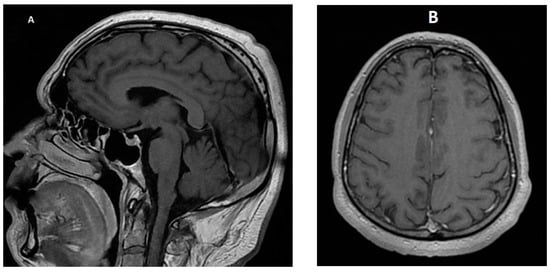

- Signs of brain sagging include flattening of the ventral pons, effacement of the prepontine and perichiasmatic cisterns, or downward displacement of the cerebellar tonsils and brain stem [5,8], which may mimic Chiari type 1 malformation. However, in SIH, the tonsils maintain normal shape and do not descend more than 5 mm below the foramen magnum [37]. Moreover, the findings associated with syringomyelia would argue for the diagnosis of Chiari type 1 malformation [32].

- Pituitary gland hyperemia leads to enlargement of the gland and can be mistaken for a pituitary adenoma [5].

- Reduced optic nerve sheath diameter and thickness (normal—4.4 mm; reduced to a mean of 3.4 mm) is best measured on coronal T2-weighted images or with transorbital ultrasonography [38].